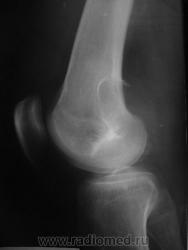

Здравствуйте, уважаемые коллеги! Сегодня в травмпункте принесли на описание снимки молодого человека 1984г.р. Травма, подвернул ногу. Жалобы характерные. Не наблюдался, не лечился. Прошу высказать мнение о характере патологии в метафизе бедренной кости.

Я склоняюсь к ГКО с кортикальным расположением, прорывом содержимого в мягкие ткани. А что думаете Вы? Т.к. снимок из травмпункта, поговорить с больным проблематично (я там совмещаю по вечерам).

какой красивый "козырек" по задней поверхности...

Расположение крупного очага деструкции эксцентрично (кзади) и вкрапления извести говорит в пользу солитарной хондромы, а местами нечеткие контуры ("скорлупа" теряется), "козырек" и  мягкоттканный компонент нацеливают на озлокачествление. Кроме того очень смущает структура прокс. эпиметафиза б/берц. кости. В любом случае, вижу прямые показания к активным действиям, начиная с биопсии.